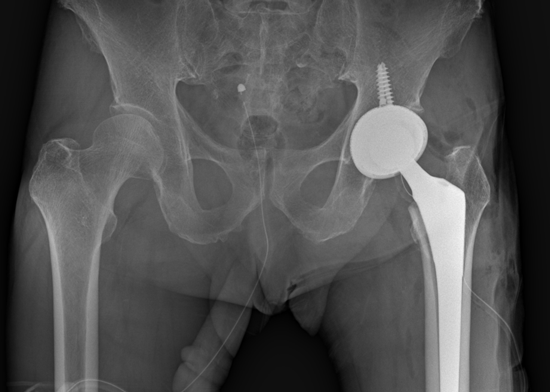

- 인공관절 치환술

괴사가 심하고 퇴행성 변화가 진행된 후에는 손상된 관절을 제거하고 인공관절로 대체하는 치료가 필요합니다. 가장 결과가 확실하며 많이 시행되는 치료법으로, 손상 범위에 따라 부분치환술, 전치환술 등으로 구분할 수 있습니다.

(좌) 대퇴골두 무혈성 괴사 수술 전 |

(우) 대퇴골두 무혈성 괴사 인공관절 수술 후 |